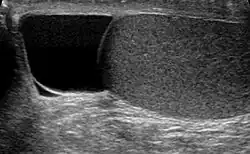

Ultrasound of a testicle (grey) and a spermatocele (black).

The primary care physician may diagnose and manage benign causes of scrotal masses such as hydrocele, varicocele and spermatocele. However, if a "must not miss" diagnosis related to testicular masses such as testicular torsion, epididymitis, acute orchitis, strangulated hernia and testicular cancer is suspected, the family physician must refer to a urologist.[19] Finding a painless, cystic mass at the head of the epididymis that is clearly separate from the testicle can indicate a spermatocele. Shining a light through the mass, a process known as transillumination, can also help differentiate between a fluid-filled cyst and a tumor, which would not allow as much light to pass.[20] If uncertainty exists, ultrasonography of the scrotum can confirm the presence of a spermatocele.[7] The location and history of any scrotal masses are crucial in determining whether or not the mass is benign or malignant.[21] Lab tests such as a complete blood count (CBC test) or urine test can also be conducted to check for any possible infection or signs of inflammation.[22]